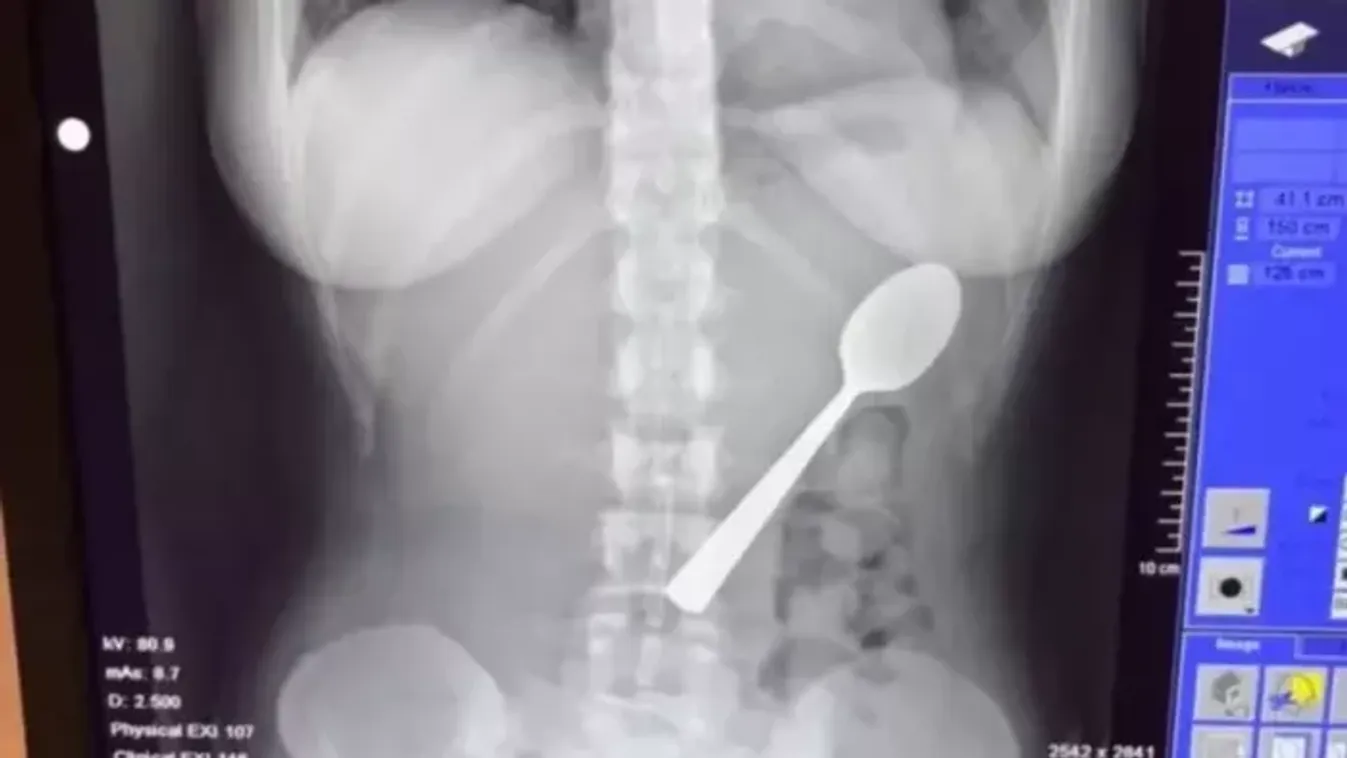

Magyar vizslája ugrott az ölébe, 17 centis kanalat kellett kiszedni a nő gyomrából